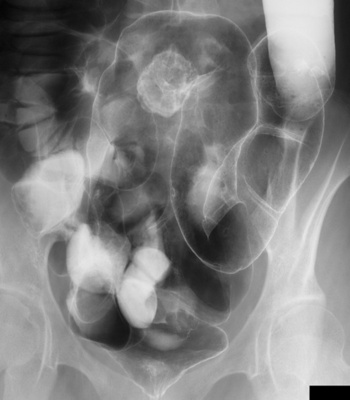

前列腺是男性重要的腺体之一,对男性健康有着举足轻重的地位。如果前列腺遭到炎症的侵害,后果则会很严重。很多男性朋友在出现前列腺炎都会去治疗,但是有不少的男性朋友都会在治疗后出现前列腺炎总是复发的现象,那么为何前列腺炎总是复发呢?针对这个问题,我们一起来看看承德现代男科医院男科医生的分析。

承德现代男科医院医生指出,其实前列腺结构的特殊性是导致很多男性在治疗炎症的时候感觉到困难的,在前列腺外面有一层脂质层,在进行简单的物治疗时,因为脂质层通透性低,物很难进入腺体中,往往只能是将腺体外的炎症消除,但是腺体内的无法消除,导致前列腺炎治愈一段时间后又发作。

同时,承德现代男科医院医生指出及时治疗此病,选择正规专业的医院很重要!前列腺炎难以治疗的主要原因是男性前列腺外都有坚韧的脂质包膜,会阻止物进入腺体发挥作用,因此,治病前列腺炎必须要选择正规专业的医院。免费咨询电话:0314-2190255.